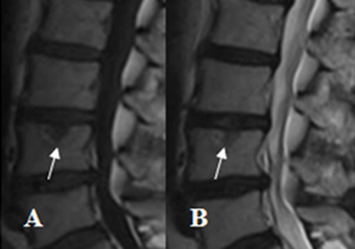

Fig 59 H. Espondilodisquitis.

A: RM sagital en T1 y B: RM sagital en T2. Erosión en la placa terminal inferior de L4, de bordes hiperintensos en ambas secuencias.

Fig 59 I. Espondilodisquitis.

A: RM sagital en T1 y B: RM sagital en STIR. Igual paciente anterior. Además de la erosión en la placa terminal inferior de L4, un año después, se identifica otra en L5. Tienen localización central y en ambos casos se aprecian cambios inflamatorios agudos.